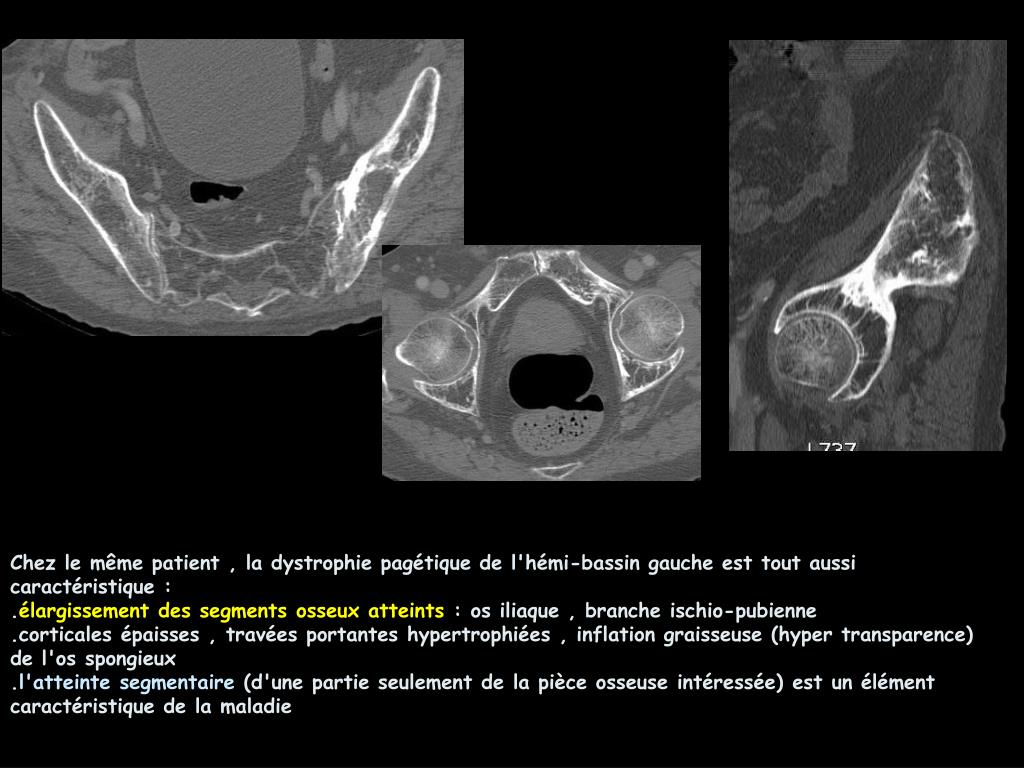

Coolest Apport Du Scanner Multibarrettes Dans Les Traumatismes Du Bassin Ppt Video Online Telecharger